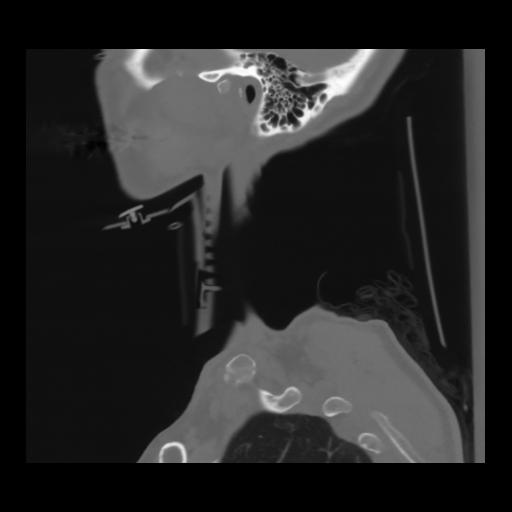

14 P.BLANDAS,,Sagittal,2.000,P.BLANDAS,Sagittal,